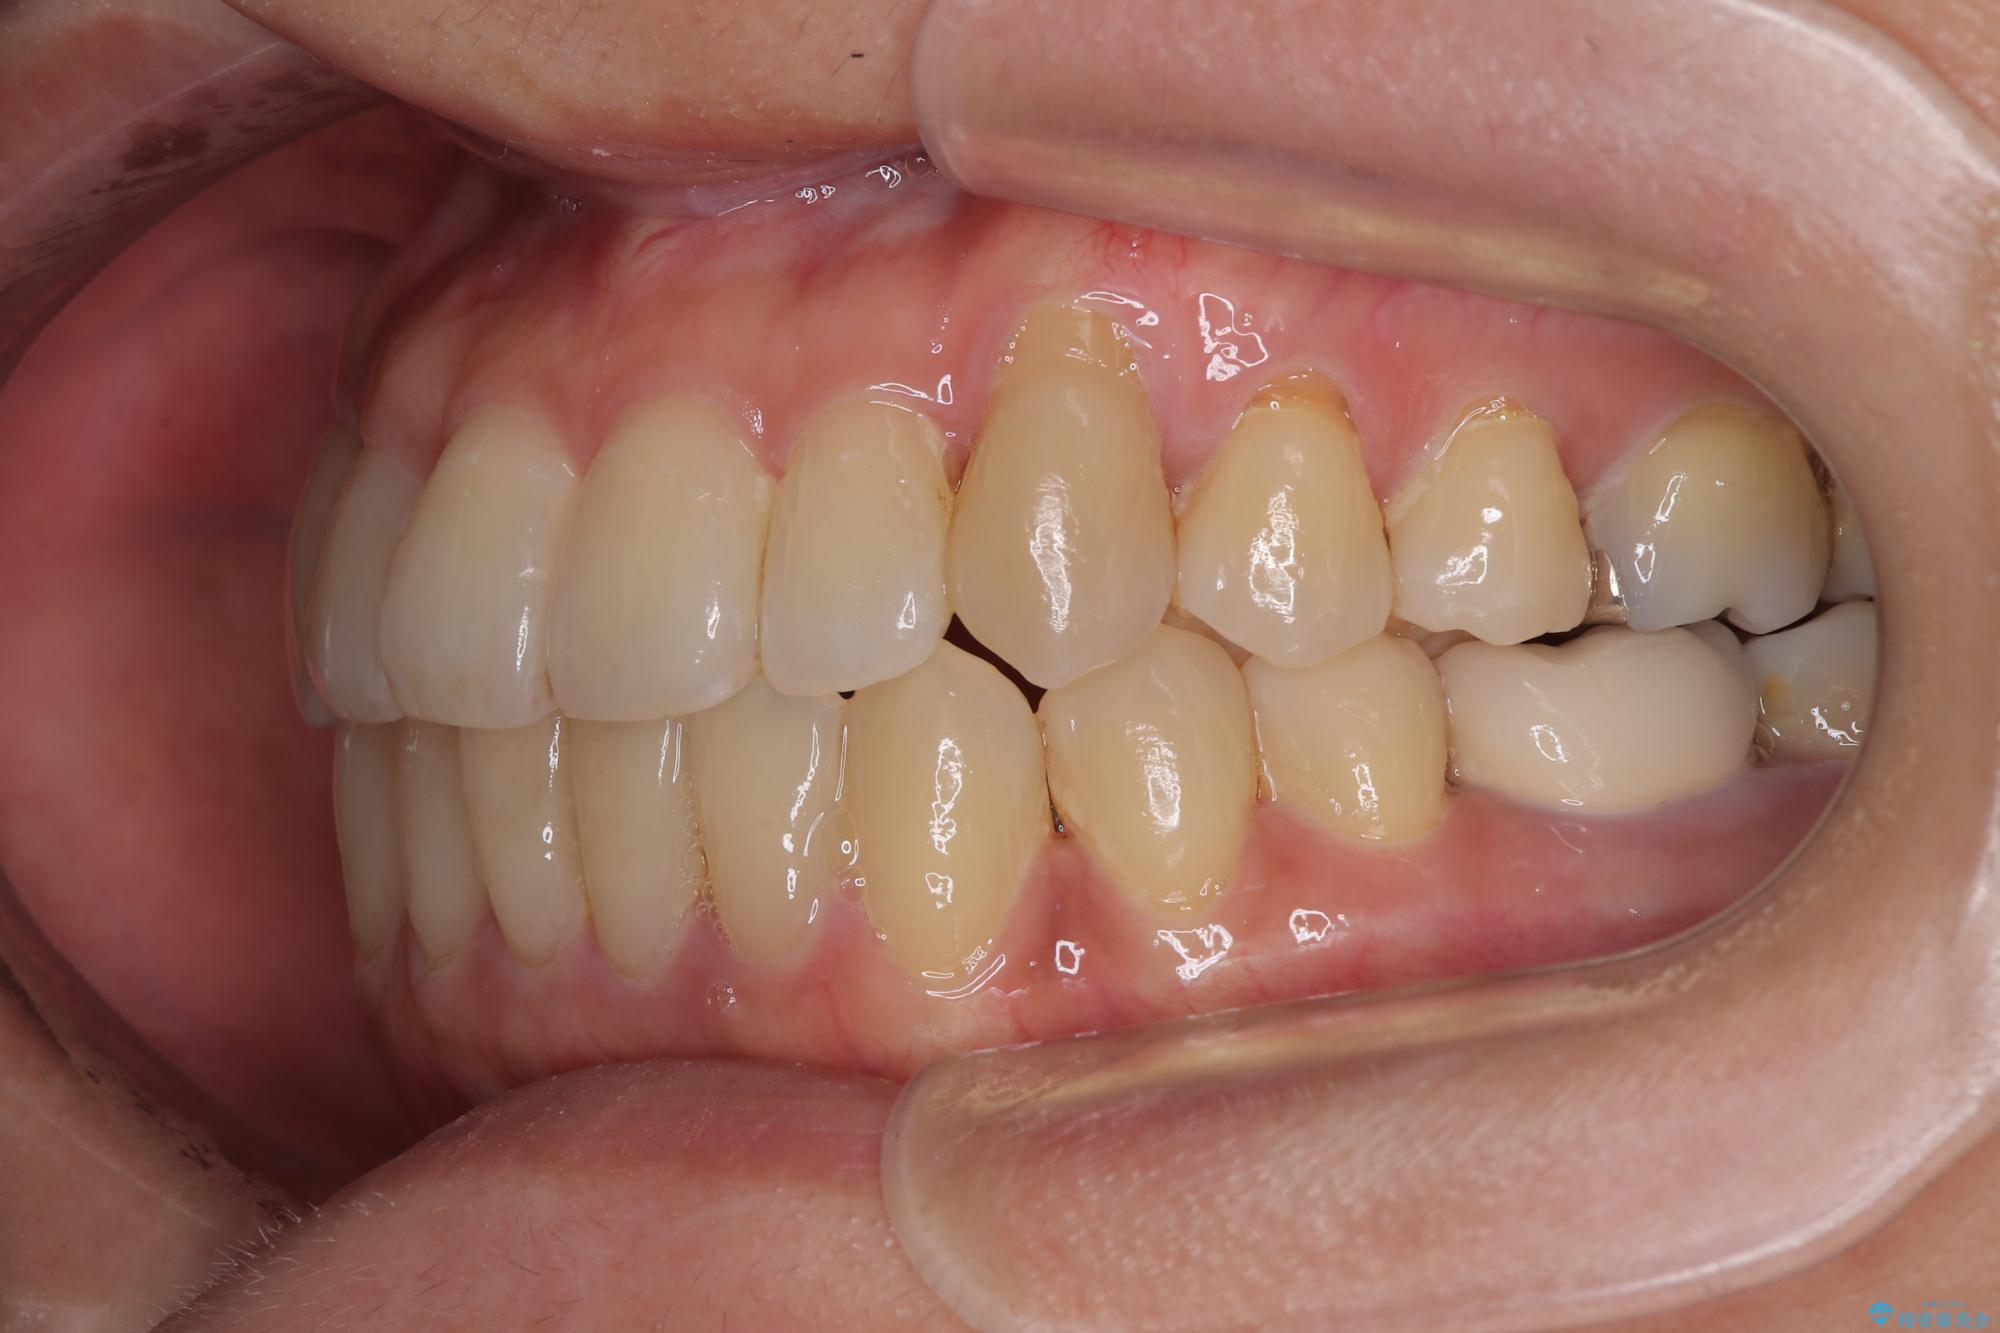

- 前歯のデコボコや八重歯を治したいとのことで来院された患者様です。

受け口傾向の骨格であり、前歯はクロスバイトまたは切端咬合となっており、下顎を中心に歯列全体の後方移動を行い、IPR(歯と歯の間を削る)によってデコボコが解消するように設計し、インビザラインにより治療を行うこととしました。